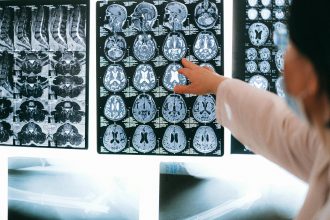

Clinicians and therapists study brain anatomy to predict how a patient’s symptoms may evolve. A person with frontal lobe damage may require behavioral and decision-making support; someone with temporal lobe damage might need help with language or memory cues.

Families can also benefit from understanding anatomy — it turns confusion into clarity, helping them interpret why their loved one behaves or feels differently after injury. Knowledge empowers caregivers to communicate effectively with medical teams and recognize early signs of complications.